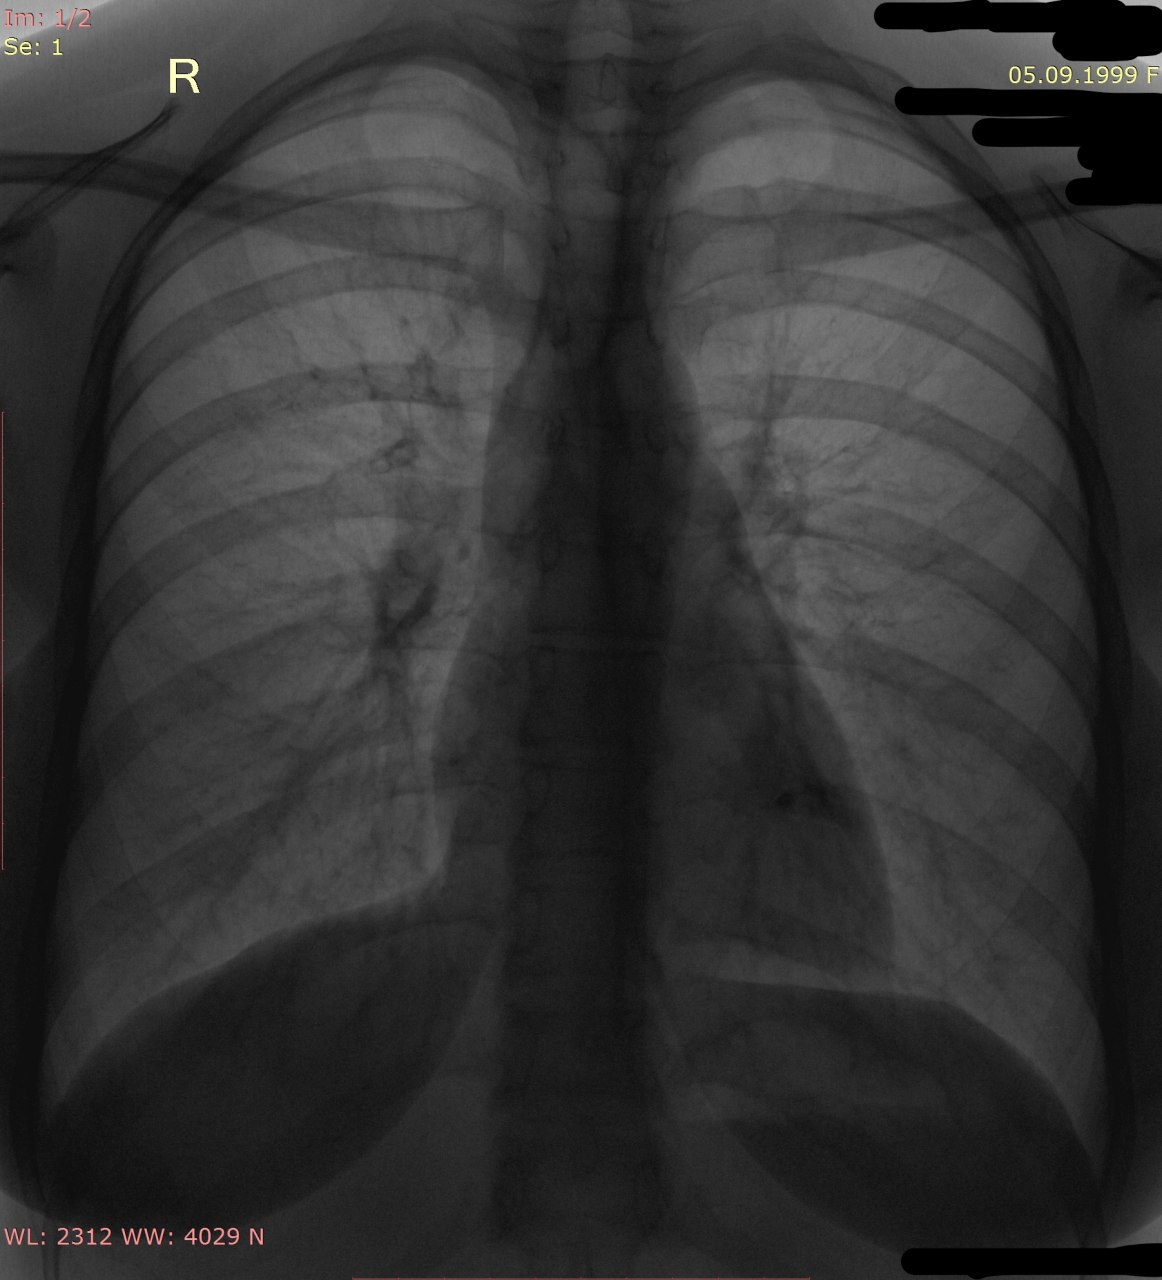

Что с позвоночником? Слишком уж угол острый для сколиоза

К сожалению не сделали боковой проекции

ВК

Добрый день! Вчера поднялась температура до 39. Больше анамнеза нет

ВК

Смущают эти тени. Это суммация теней или инфильтрация все-таки?

ВМ

Суммарная